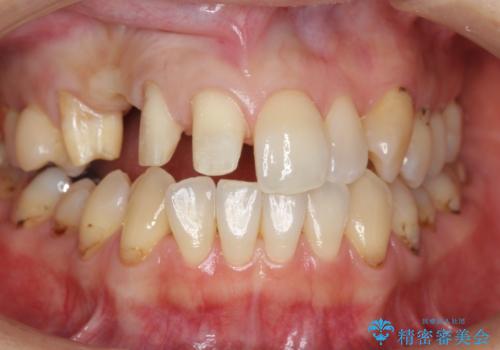

前歯の虫歯 とりあえずつけていた歯がとれた

- 右上の歯はもともとなかったが、ブリッジにするのが嫌でプラスチックの歯を応急的に接着剤でつけていたのがとれてしまったとのことでした。

接着剤で留めてある周りが、虫歯になってしまっていました。

初めはブリッジにすることに抵抗があったようですが、とりあえずでくっつける汚い状態ですと虫歯のリスクが非常に高いことをご説明しました。